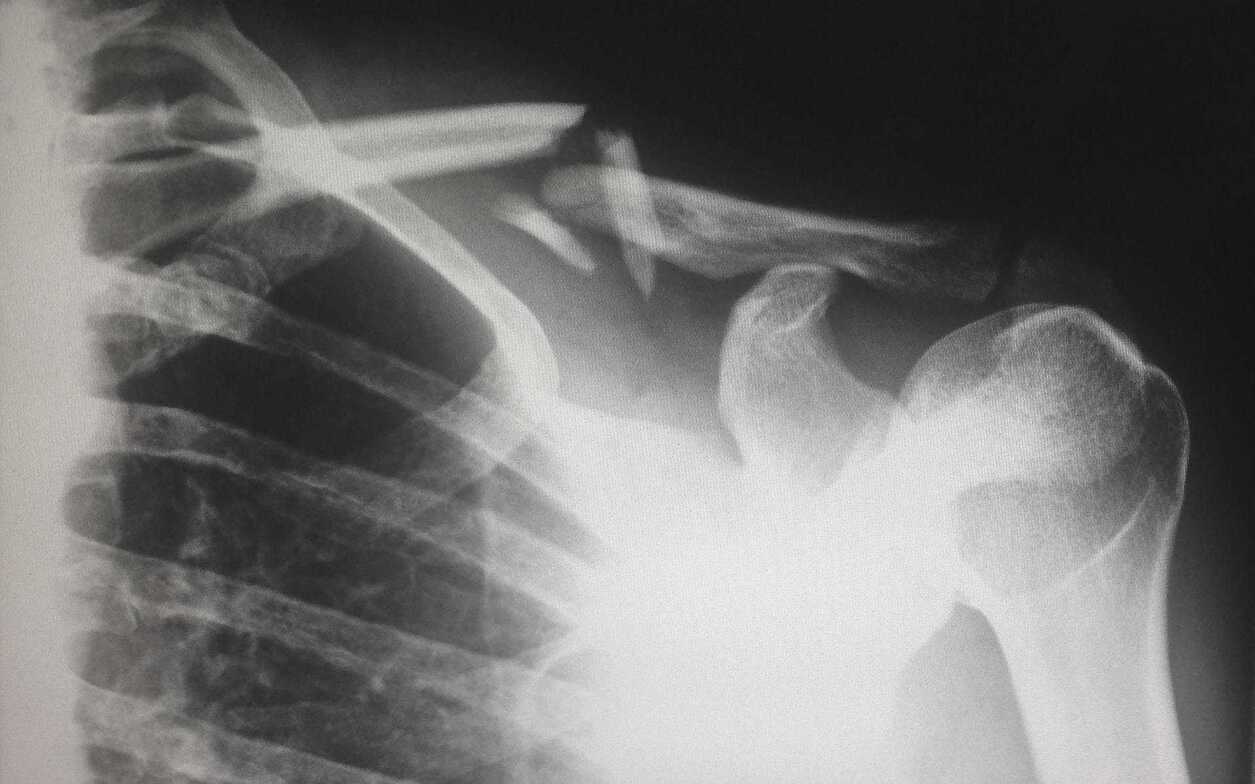

The New York Times had an article recently on bone density.

They concluded’ “After 16 weeks of high-impact jump training, hip BMD can be improved in premenopausal women by jumping 10 or 20 times, twice daily, with 30 seconds of rest between each jump, compared with controls.”